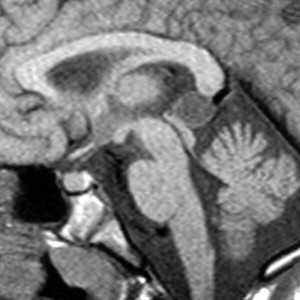

Коллоидная киста - это врождённое нейроэпителиальное образование. Коллоидная киста выстлана эпителием и имеет фиброзную капсулу. Она составляют около 1-2% объемных внутричерепных образований. Обычно диагностируются в возрасте между 30 и 50 годами. При МРТ головного мозга видно, что киста всегда расположена в переднее-верхнем отрезке III желудочка между отверстиями Монро. Контур ее четкий, форма округлая, содержимое бывает неоднородное. Размер от 3 мм до 4 см, при больших размерах она закрывает отверстия Монро и вызывает окклюзионную гидроцефалию. Сигнал зависти от примеси белка к ликвору. При наличии белкового мукоидного содержимого киста гиперинтенсивна на Т1-взвешенных МРТ и гипоинтенсивна на Т2-взвешенных МРТ, но встречаются варианты гиперинтенсивные на томограммах обоих типов кольцевидные или смешанные . Контрастирования не наблюдается.

КТ и МРТ головного мозга. Коллоидная киста III желудочка.